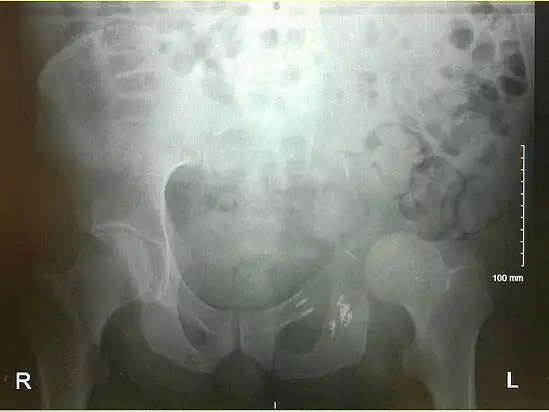

An x-ray of a limb-sparing hemipelvectomy on the left side of a male pelvis taken one month after surgery.